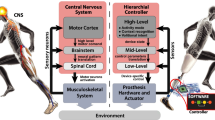

One of the greatest applications scrutinized in the perspective of sEMG interfaces is the EMG prostheses as evident from an immense expanse of research chronicles [36,37,38,39,40,41,42,43,44,45,46]. Established by the Central Prosthetic Research Institute of the USSR in 1960s, the first commercial prosthetic arm was a revolutionary step in the arena of sEMG applications in upper limb prostheses (ULP) [4]. This prosthetic arm included one DOF (open and close) which used strong antagonistic muscle contractions for control action. Regardless of the fact that the realization of high classification accuracies for about twelve classes [25, 47] has been reported in erstwhile sEMG investigations, the contemporary sEMG-based ULP employ the classical threshold-based concepts. On–Off control based on threshold is one of the easiest methods for control which actuates the desired function whenever a preset value of threshold falls below the sEMG amplitude. In addition, different channels positioned over physiologically apt muscles can be allotted different functions. Nonetheless, for controlling one DOF (such as hand opening or closing), as a minimum, two signal sites are needed. Moreover, the series of muscle activity (starting from the threshold and terminating at the value of maximal muscle contraction) may be separated among numerous intervals such that each interval links to a specific prosthetic function [48]. Rate coding (which involves utilization of speed of the muscle contraction) and pulse coding (which utilizes pulses of sEMG activity as the control command) are two more strategies employed in commercial prostheses [48]. After the introduction of the advanced ULP, the markets were flooded with multiple-DOFs based prostheses as shown in [34]. These systems ensure control of DOFs in a sequential and consecutive manner. Unintuitive movements are necessary for the production of two sEMG control signals (one for using both DOFs and the other for switching between two DOFs). For switching between different DOFs, co-contractions are required. One of the major limitations of this approach is the incapability of concurrent control of multiple joints and increased complexity with increasing number of DOFs. Some of the major advancements and pioneering investigations in the field of sEMG-based prostheses have been discussed in the following sub-sections. More specifically, we present the review results for both upper and lower limb prostheses detailed in many aspects, as illustrated in Fig. 4.

The indispensable constituents of robotic leg prosthesis [130] have been presented in Table 6. Also, the generalized framework for active lower limb prostheses/orthoses (P/O) control [131] has been illustrated in Fig. 5. This sketch reveals the physical interface and signal-level feedback paths involved in the real-time application of powered assistive devices.